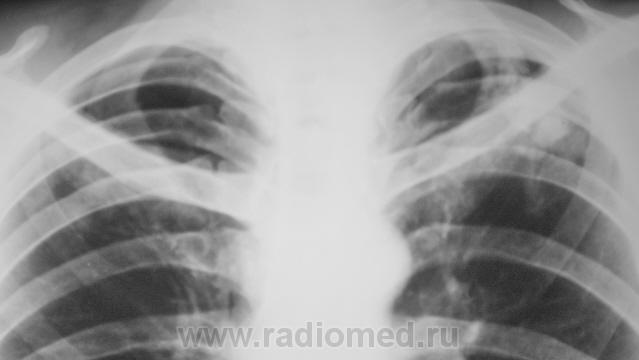

Пациент на учете. Направлен фтизиатром, как «клиническое излечение».

Конгломеративная туберкулома для фтизы уже считается пустяком.

Следовательно, "клиническое излечение"?

Вернее, наверное, будет сказано "стадия ремиссии". Неизвестно, когда такая туберкулома может "бахнуть". Особенно, если она по типу "заполненной каверны".

Конгломератные каверны образуются обычно вследствии инфильтративного tbc, опасности тут поменьше...

Это клиническое отреченение! Оставлена мина замедленного действия. Торакальным хирургам надо работать даже через « не могу».